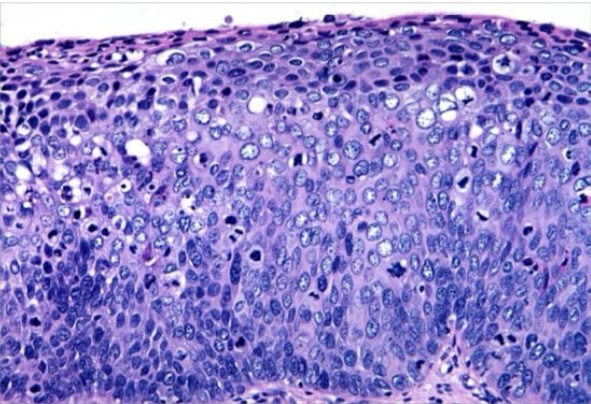

Ballooning degeneration

Hydrophic degeneration